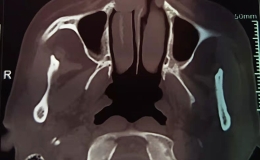

目前科室开放床位9张,临床医生3名,其中主治医生1名,住院医生2名,从1997年起三名医生分别在省立医院、安医及名人眼科医院进修一年,经过多年的努力,能够对眼耳鼻喉各类常见病、多发病以及疑难危重病人给予正确及时的处理,科内从未发生医疗事故及医疗纠纷。目前眼耳鼻喉科有手术显微镜2台,眼科A/B超1台,裂隙灯2台,手持式进口眼压仪1台,眼检镜1台,电子喉镜1台,纯音听力计1台,微波治疗仪以及各类手术器械,能够满足眼耳鼻喉科疾病的各类检查,治疗和手术需要。2002年寿县中医医院眼耳鼻喉科担任了残联举办的“光明行”活动,圆满完成白内障复明术100例,取得良好的社会效益。从2006年起,寿县中医医院眼耳鼻喉科与省级医院眼科建立了良好的合作关系,依托省级医院技术设备优势,在我县率先开展超声乳化术治疗白内障,与专家合作完成“白内障摘除术+人工晶体植入术”1000余例,均取得良好的手术效果,方便病人治疗,取得广大白内障患者的高度评价。我院眼耳鼻喉科于2012年5月通过省卫生厅及省级医院专家组考核,取得了高度赞誉,并顺利取得白内障复明工作定点医院资格。